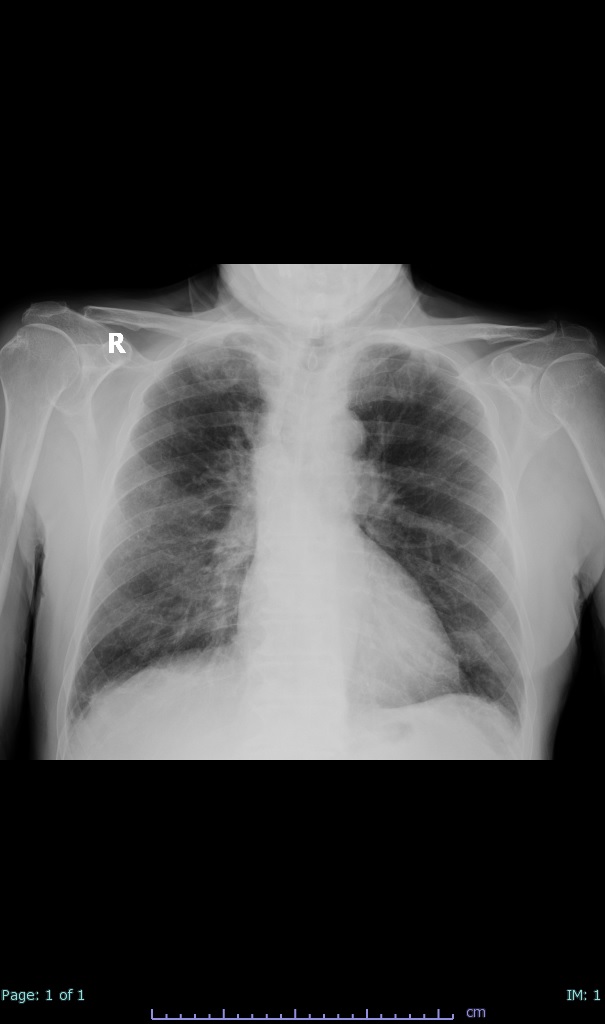

- 100% subpleural involvement, 33% + centrolobular involvement

- 40% even apical/basilar, 27% basilar dom, 5% mid dom. 1/17

- 66% had some + CXR finding I could correlate to a CT finding